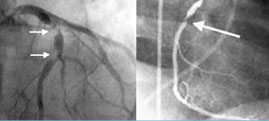

Η τεχνική συρραφής ενός μοσχεύματος σε μια στεφανιαία αρτηρία φαίνεται στο σχήμα

Εγχείρηση αορτοστεφανιαίας παράκαμψης σε πάλλουσα καρδιά

Σχετικά νέα εγχειρητική τεχνική αορτοστεφανιαίας παράκαμψης, κύριο χαρακτηριστικό της οποίας είναι ότι η καρδιά παραμένει σε λειτουργία, και δεν χρησιμοποιείται η εξωσωματική κυκλοφορία.

Κατά την κλασσική μέθοδο αορτοστεφανιαίας παράκαμψης η καρδιά σταματά να συστέλλεται και η κυκλοφορία του αίματος γίνεται με τη βοήθεια του ειδικού μηχανήματος της εξωσωματικής κυκλοφορίας.

Η μέθοδος αυτή ονομάζεται αορτοστεφανιαία παράκαμψη σε πάλλουσα καρδιά (beating heart surgery), εφαρμόζεται από το 1990 και σήμερα αποτελεί πρακτική ρουτίνας ορισμένων καρδιοχειρουργών. Οι χειρουργοί που την εφαρμόζουν πιστεύουν ότι πρέπει να τύχει ευρύτερης αποδοχής, αν και υπάρχουν αντικρουόμενες απόψεις για την αποτελεσματικότητα της. Στα μειονεκτήματα της περιλαμβάνονται η έλλειψη πολύχρονων μελετών για τη μακροπρόθεσμη βατότητα των μοσχευμάτων και τη συμβολή της στη μακροχρόνια επιβίωση του ασθενούς. Το σίγουρο είναι ότι η τεχνική αυτή έχει ένδειξη σε ασθενείς με σοβαρή ασβέστωση της ανιούσης αορτής, επηρεασμένη νεφρική ή αναπνευστική λειτουργία ή ασθενείς με ιστορικό εγκεφαλικού επεισοδίου στο παρελθόν.